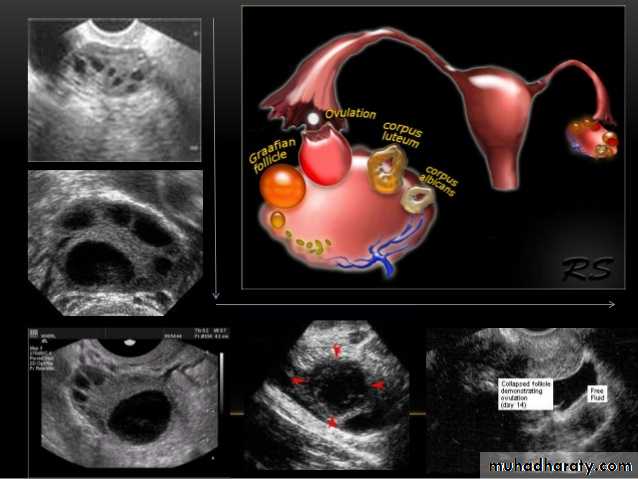

Ovarian cysts :

Ovarian cysts are commonly encountered in gynecological imaging, and vary widely in etiology, from physiologic, to complex benign, to neoplastic.Small cystic ovarian structures should be considered normal ovarian follicles unless the patient is pre-pubertal, post-menopausal, pregnant, or the mean diameter is >3.0 cm

Radiographic features

Ultrasound is usually the first imaging modality for assessment of ovarian lesions. Simple ovarian follicular cysts are:

anechoic

intraovarian or exophytic;

have an imperceptible wall

Polycystic ovarian syndrome (PCOS) is a chronic anovulation syndrome. Sonographic findings alone are not specific, and the diagnosis is made on the combined clinical, biochemical and sonographic grounds

The classic triad of PCOS is:

oligomenorrhea

hirsutism

Obesity

Ovaries

may show sonographic features of polycystic ovaries

bilateral enlarged ovaries with multiple small follicles: 50%

increased ovarian size (>10 cc)

12 or more follicles measuring 2-9 mm

follicles of similar size

peripheral location of follicles: which can give a string of pearl appearance

hyperechoic central stroma

the ovarian outline may be slightly irregular.